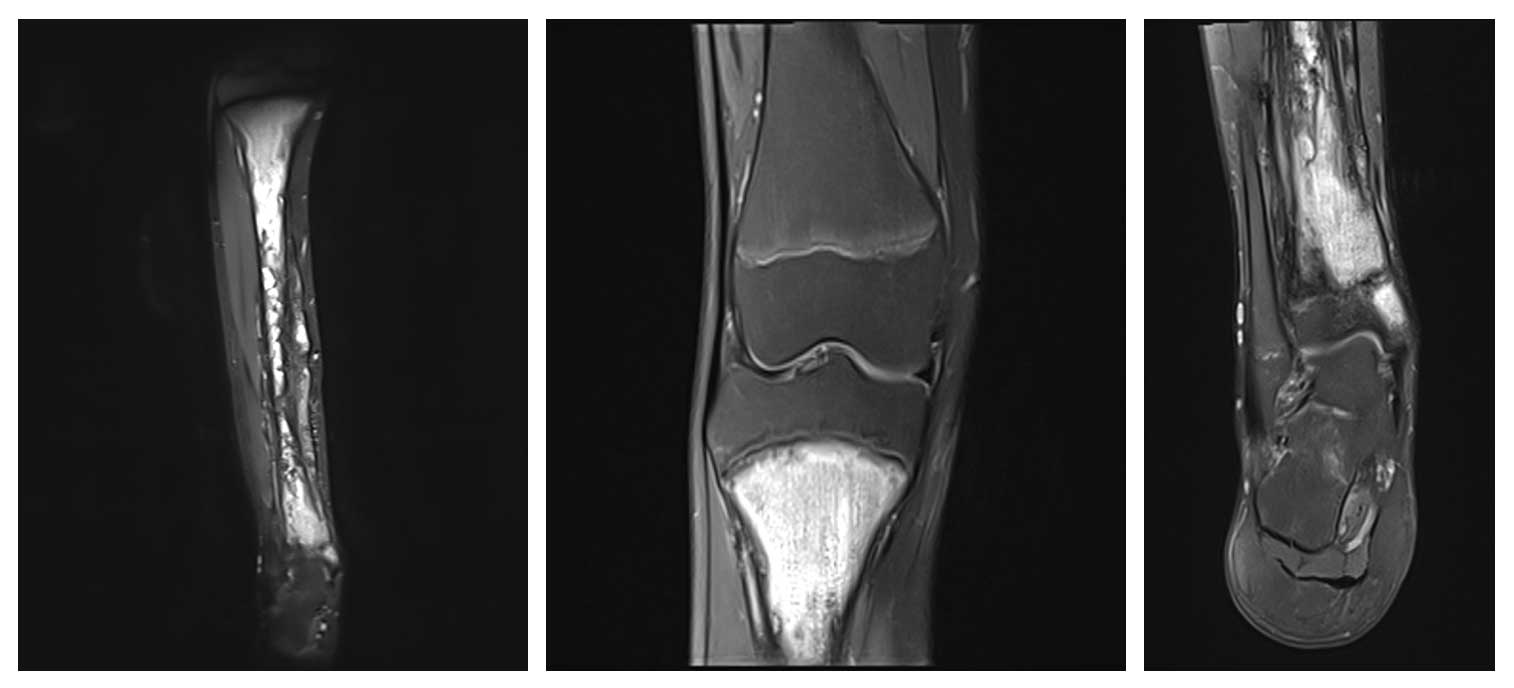

14 yaş erkek hasta, sağ kaval kemiğinde (tibia) ağrı ve şişlik şikayetleriyle başvurdu. Yapılan radyolojik incelemelerde tibianın büyük kısmını tutan osteosarkom saptandı.

Ameliyat Öncesi: MR’da tibianın üst epifizi hariç tamamını tutan tümör dokusu görülmekte.